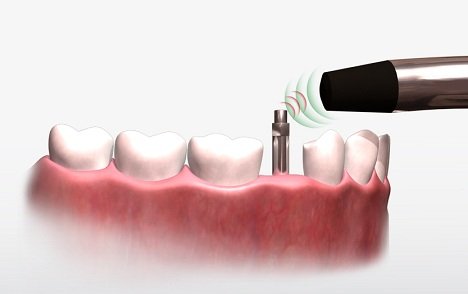

Osstell es una herramienta que se utiliza en la DentArt para asegurarnos de que los implantes dentales están estables y bien oseointegrados.

Por medio de pulsos magnéticos se medirá la frecuencia de vibración del Implante Dental dando como resultado un valor de estabilidad, entre mayor sea ese valor, menor va a ser el tiempo de cicatrización o oseointegración del implante dental existiendo la posibilidad de colocar los dientes inclusive en la misma sesión en que colocaron los implantes.

Este instrumento hace que sea más fácil para los dentistas decidir cuándo es el mejor momento para cargar los implantes.